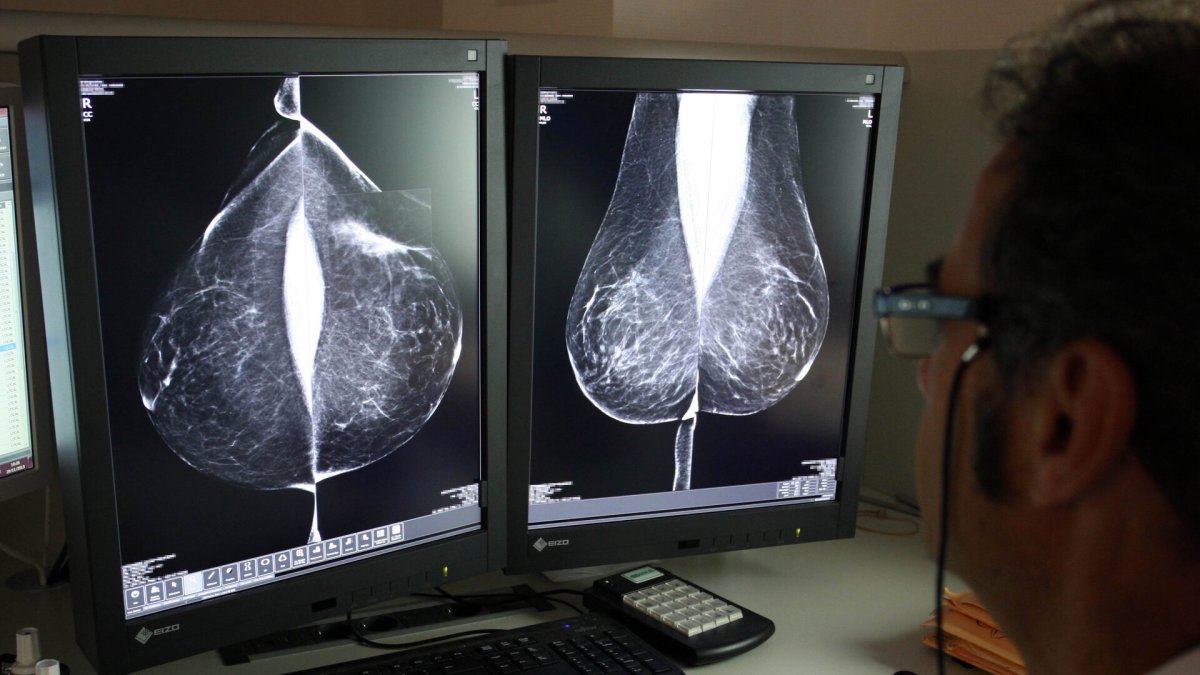

Estudio una mamografía digital, en el servicio de mamografías del Hospital Río Hortega de Valladolid.

Inteligencia artificial para detectar lo que se le puede escapar al ojo humano. La sanidad pública de Castilla y León realizará una inversión la que la IA 'revise' pruebas diagnósticas y pueda mejorar la detección de ciertas patologías como el cáncer de mama o problemas cardíacos o pulmonares.

La Consejería de Sanidad prevé invertir más de 3,3 millones de euros en el primer semestre de este año para incorporar la inteligencia artificial a la lectura de mamografías y radiografías torácicas. Con este paso permitirá a los profesionales de Sacyl afinar en la precisión diagnóstica y terapéutica, y mejorar los resultados en salud, así como agilizar las lecturas por medio de algoritmos certificados, con marcado de la Comunidad Europea.

Diversos estudios científicos demuestran que la inteligencia artificial se ha convertido en un aliado de los radiólogos, con un alto rendimiento en los cribados, que pueden ayudar a evaluar, en el caso del cáncer de mama, las mamografías de bajo riesgo, como también en la detección temprana de esta enfermedad, siempre como una técnica de apoyo en la toma de decisiones. Incluso, algunos ensayos indican que la inteligencia artificial es capaz de predecir el riesgo de desarrollar cáncer de mama cinco años antes de que aparezca. En concreto estas conclusiones se extraen de un modelo desarrollado por el Instituto de Tecnología de Massachusetts, que se ha probado en varios países. No obstante, los expertos coinciden en la necesidad se seguir trabajando en más estudios y ensayos prospectivos.

También, coinciden en que ayuda a la lectura, lo agiliza y puede ayudar, también, ante la falta de radiólogos. En Castilla y León el programa de de detección precoz de cáncer de mama establece un sistema de doble lectura, que implica que pasen por manos de al menos dos radiólogos. El año pasado, la Junta optó por externalizar este servicio, práctica común en el conjunto del Sistema Nacional de Salud, con el fin de agilizar la lectura de 125.000 pruebas anuales y también después de que se ampliara el rango de edad hasta los 74 años de edad. Invirtió casi cuatro millones de euros, a los que podrían sumarse este año otros 3,3 millones, con un nuevo contrato.